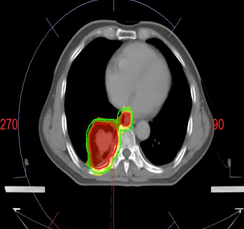

Case : Locally advanced non-small cell lung cancer

Dose Prescription:

95% PGTV 60.2 Gy/2.15 Gy/28 F

95% PTV 50.4 Gy/1.8 Gy/28 F

Protocol : RTOG0617

Techniques : IMRT/VMAT/HT